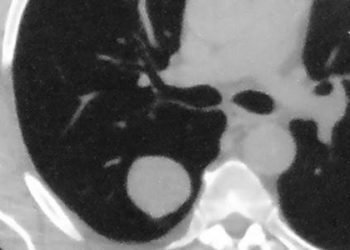

Study Rundown: Radiofrequency ablation (RFA), an effective and routine treatment for both primary and recurrent hepatocellular carcinoma (HCC), has prompted the exploration of alternatives like stereotactic body radiotherapy (SBRT), which delivers precise high-dose radiation with minimal impact on surrounding tissues. Retrospective studies suggest SBRT offers outcomes comparable to RFA. This study was the first randomized trial assessing RFA vs SBRT for recurrent HCC. The primary endpoint was local progression-free survival (LPFS) and secondary endpoints included progression-free survival (PFS), overall survival (OS), local control rate (LCR), and safety. LPFS at 3 years was 84.3% in the SBRT group vs 67.3% in the RFA group. It was found that the HR for LPFS was HR 0.45 (significant). It was found that SBRT performed better than RFA in LPFS for tumours ≤2 cm (HR 0.39, significant), however, this was not significant for larger (2-5 cm) tumours (HR 0.58, non-significant). LCR at 3 years was 92.8% for SBRT vs 75.9% for RFA with a 3-year OR 0.25 (significant). Median PFS time was 37.6 months for SBRT vs 27.6 months for RFA, with HR 0.76 (non-significant). OS at 3 years was 90.3% for SBRT vs 91.0% for RFA, with HR 0.91 (non-significant). Regarding safety, most adverse events were grade 1-2 with only 1 case of grade 3-4 events in each arm, a pneumothorax in the RFA group and thrombocytopenia in the SBRT group. The strengths of this study included the methodology, and the limitations included the small sample size. Overall, this study found that SBRT has some improved minor outcomes compared to RFA in treating adults with small recurrent HCC.

In-Depth [randomized controlled trial]: This open-label single institution trial was conducted in China and enrolled adults with recurrent small (<5cm) HCC and randomized them (1:1) to either SBRT (n=83) or RFA (n=83). Most patients (88%) had hepatitis B virus (HBV)–related HCC. Some patients received a secondary RFA if residual disease was found after the first RFA. The median radiation dose of the SBRT group was 45 Gy (IQR, 42-48) in three fractions. Median follow-up time was 42.8 (95%CI, 39.8-45.8) months in the SBRT group and 42.9 (95%CI, 40.7-45.1) months in the RFA group. LPFS at 3 years was 84.3% (95%CI, 76.5-93.0) in the SBRT group vs 67.3% (95%CI, 57.6-78.6) in the RFA group. It was found that the HR for LPFS was HR 0.45 (95%CI, 0.24-0.87, p=0.014). It was found that SBRT performed better than RFA in LPFS for tumours ≤2 cm (HR 0.39, 95%CI, 0.17-0.89, p=0.020), however, this was not significant for larger (2-5 cm) tumours (HR 0.58, 95%CI, 0.20-1.68, p=0.310). LCR at 3 years was 92.8% for SBRT vs 75.9% for RFA with a 3-year OR 0.25 (95%CI, 0.09-0.65, p=0.005). Median PFS time was 37.6 (95%CI, 26.0-49.2) months for SBRT vs 27.6 (95%CI, 20.3-34.8) months for RFA, with HR 0.76 (95%CI, 0.50-1.15, p=0.190). OS at 3 years was 90.3% (95%CI, 83.7-97.5) for SBRT vs 91.0% (95%CI, 84.8-97.6) for RFA, with HR 0.91 (95%CI, 0.37-2.22, p=0.830). With regards to safety, most adverse events were grade 1-2 with only 1 case of grade 3-4 events in each arm, a pneumothorax in the RFA group and thrombocytopenia in the SBRT group. Overall, this study found that SBRT has some improved minor outcomes compared to RFA in treating adults with small recurrent HCC.